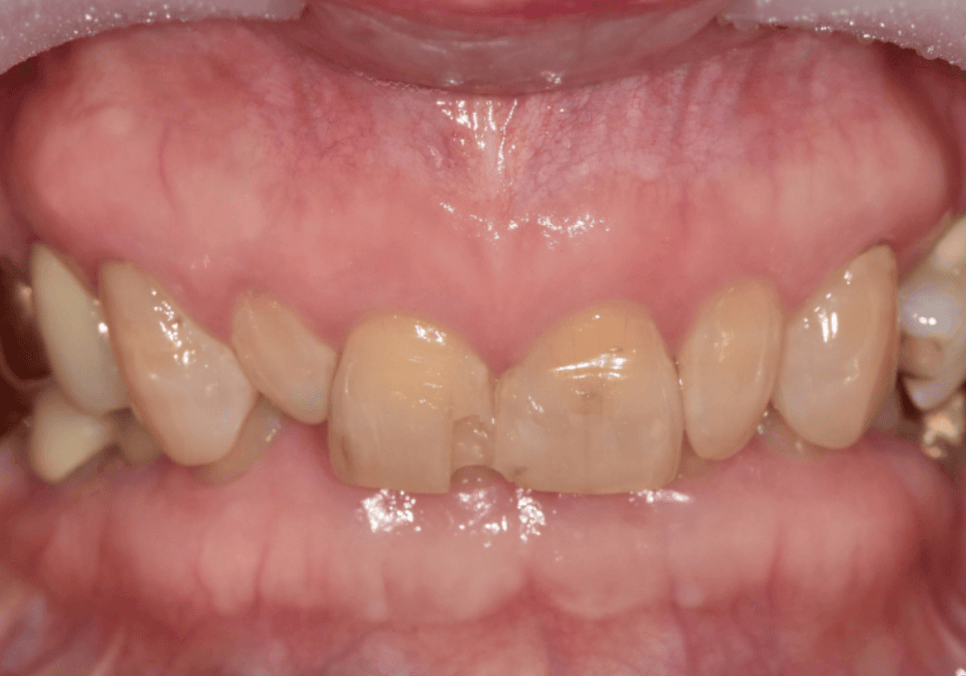

여기에 또 하나의 문제가 있었습니다.

이 분은

윗니가 아랫니를 70~80% 정도 깊게 덮고 있는

과개교합을 가지고 계셨어요.

이렇게 깊게 물리는 고합의 경우,

아래 앞니 끝이 윗니 뒤쪽과 레진에

반복적으로 부딪힐 수밖에 없어요.

250304

그러니 레진을 다시 메워도

조금 시간이 지나면

또 깨지고 떨어질 수밖에 없었던 거였죠.